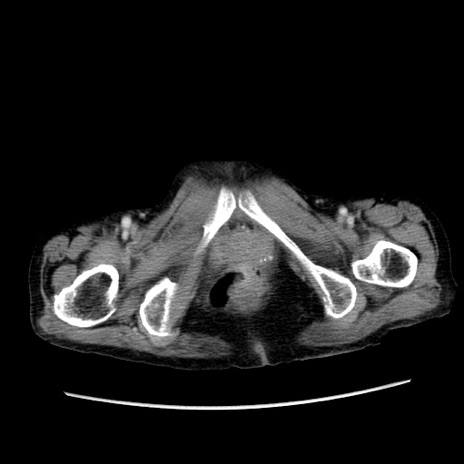

症例25(横断像)

【症例】80歳代女性

【主訴】胸のつかえ感

【現病歴】約9時間前に食後から胸のつかえた感じあり、嘔吐あり、来院。

【既往歴】胃癌(全摘)、胆摘、虫垂炎

【身体所見】心窩部に圧痛あり、反跳痛なし。

【データ】WBC 5700、CRP 0.05